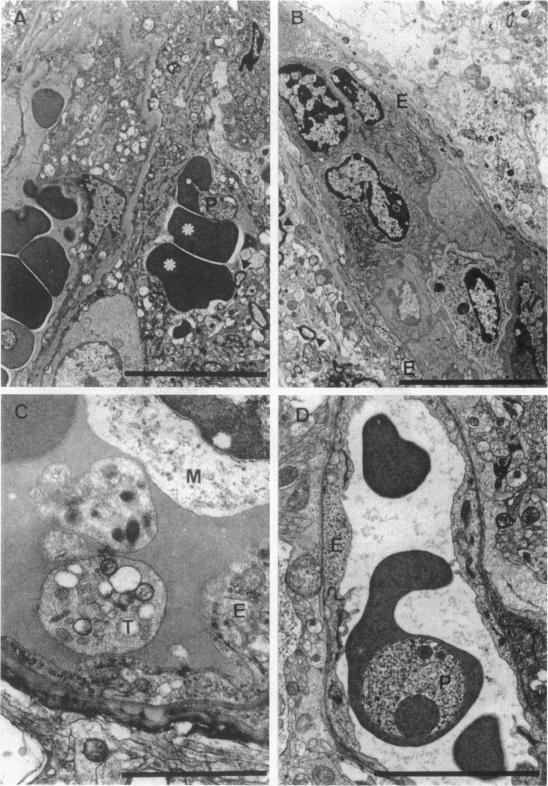

Tumor necrosis factor (TNF) induced by Plasmodium berghei ANKA (PbA) infection was suggested to play an important role in the development of cerebral malaria (CM). We asked whether TNF-alpha/beta double-deficient mice, which have a complete disruption of the TNF-signaling pathways, are protected from CM and what might be the possible mechanisms of protection. PbA infection induces fatal CM in wild-type mice, which die within 5 to 8 days with severe neurological signs. In contrast, TNF-alpha/beta-deficient mice are completely resistant to PbA-induced CM. As PbA-induced up-regulation of endothelial intercellular adhesion molecule (ICAM)-1 expression as well as the systemic release of nitric oxide is found only in wild-type mice, TNF is apparently central for the recruitment of mononuclear cells and microvascular damage. Mononuclear cell adhesion to the endothelium, vascular leak and, perivascular hemorrhage are found only in the brain of wild-type mice. By contrast, the development of parasitemia and anemia is independent of TNF. Resistance to CM in TNF-alpha/beta-deficient mice is associated with reduced interferon-gamma and interleukin-12 expression in the brain, in the absence of increased T helper type 2 cytokines. In conclusion, TNF apparently is required for PbA-induced endothelial ICAM-1 up-regulation and subsequent microvascular pathology resulting in fatal CM. In the absence of TNF, ICAM-1 and nitric oxide up-regulation are reduced, and PbA infection fails to cause fatal CM.

伯氏疟原虫ANKA株(PbA)感染诱导产生的肿瘤坏死因子(TNF)被认为在脑型疟疾(CM)的发展过程中起重要作用。我们研究了TNF-α/β双缺陷小鼠(其TNF信号通路完全被破坏)是否对CM具有抵抗力,以及可能的保护机制是什么。PbA感染在野生型小鼠中诱发致命的CM,这些小鼠在5至8天内死亡,并伴有严重的神经症状。相比之下,TNF-α/β缺陷小鼠对PbA诱导的CM完全具有抵抗力。由于仅在野生型小鼠中发现PbA诱导的内皮细胞间黏附分子(ICAM)-1表达上调以及一氧化氮的全身释放,因此TNF显然是单核细胞募集和微血管损伤的关键因素。单核细胞与内皮细胞的黏附、血管渗漏以及血管周围出血仅在野生型小鼠的脑中出现。相比之下,疟原虫血症和贫血的发展与TNF无关。TNF-α/β缺陷小鼠对CM的抵抗力与脑中干扰素-γ和白细胞介素-12表达降低有关,同时辅助性T细胞2型细胞因子并未增加。总之,TNF显然是PbA诱导内皮ICAM-1上调以及随后导致致命CM的微血管病理过程所必需的。在没有TNF的情况下,ICAM-1和一氧化氮的上调减少,并且PbA感染不会导致致命的CM。